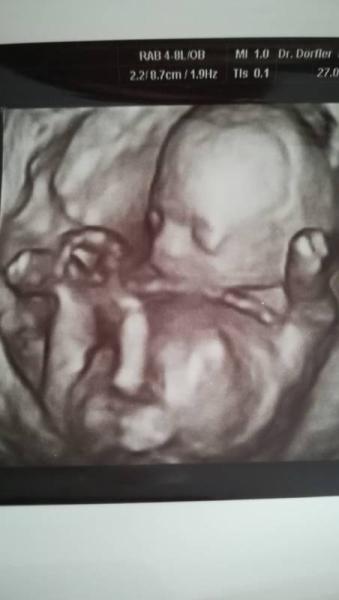

Hallo bin in der 19 ssw und der arzt hat in der 12 und 17 ssw gesagt es wird ein junge, was meint ihr kann ich mich da festbinden oder kann sich noch was ändern, wie war es bei euch? Ich tu ein Foto rein für die erfahrenen Mamas, ich sehe da zwar auch ei Zipfel aber keine Ahnung ob ich es richtig sehe danke LG

Sorry hab mich grad angemeldet und komm nicht so zurecht noch, also ich bin 19 ssw und vor 2 wichen war ich bei. Arzt. hab mich irgendwie vertippt oben neben meinen usernamen und finde e nicht den weg wie ich es korrigieren soll, photo hab ich dazu getan doch will nicht h erscheinen ben daher probiere ich es nochmal

Na ich würde sagen eindeutig ein junge meine Buben haben sich auch früh gezeigt. LG nita

Ich finde auch dass es total nach Junge aussieht.

Das sieht sehr nach einem Jungen aus.